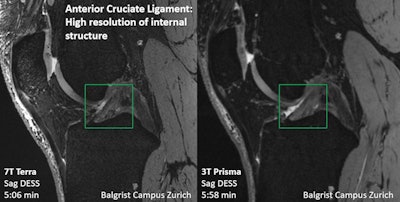

Finally, Sutter reviewed a number of possible clinical implementation directions for 7-tesla MRI, describing how it improved treatment planning in a 52-year-old woman involved in a skiing accident: 1.5-tesla MRI showed an anterior cruciate ligament (ACL) tear and a nondisplaced fracture of the tibial head, and she was referred for conservative treatment. However, 7-tesla MRI revealed a more complex tear and a meniscal ramp lesion, which directed her to surgery. In another case, 7-tesla MRI identified delamination of femoral cartilage in a 41-year-old male snowboarder that 1.5-tesla MRI missed.

"[Studies have shown] that 7T MRI has higher diagnostic accuracy when it comes to visualizing low-grade meniscus and cartilage damage, and that [the technology] can be superior to 3T MRI for detecting small calcifications in articular cartilage and menisci," he said.